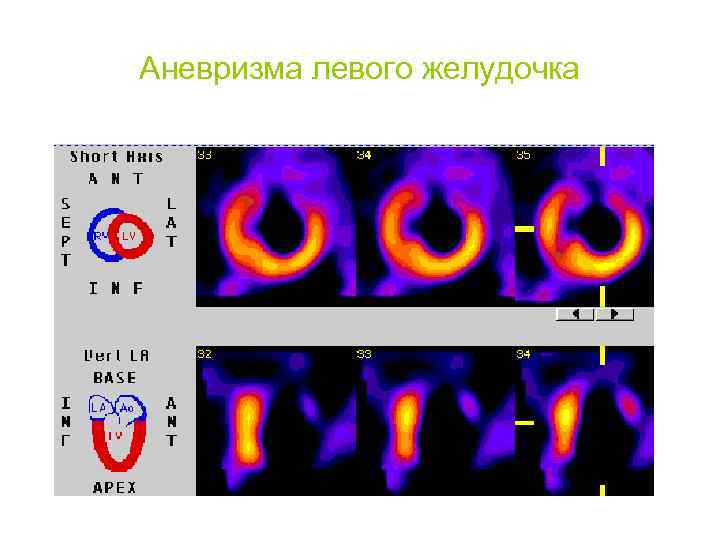

Аневризма левого желудочка

Аневризма левого желудочка